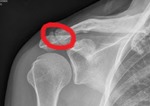

Подскажите, пожалуйста, к какому врачу обратиться с болями в АКС (акромиально-ключичного сочленения), чтобы хотя бы диагноз верный узнать? Вот отметила где болит, при долгих нагрузках начинает болеть и вся ключица.